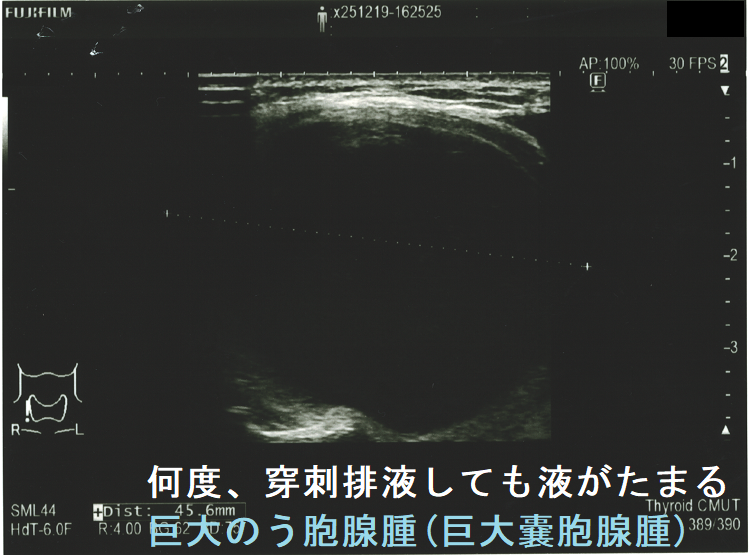

手術すべきか迷う巨大甲状腺のう胞腺腫(巨大甲状腺嚢胞腺腫)。横径 5.49cmで、ほぼ6cm。80歳以上なら全身麻酔のリスクを冒してまで手術しなくて良いかもしれません。せいぜい次項の経皮的エタノール注入療法(PEIT)ぐらいでしょう。

頻回に穿刺排液しても液がたまる巨大のう胞腺腫(巨大嚢胞腺腫)は、良性腫瘍(のう胞型濾胞腺腫:嚢胞型濾胞腺腫)であっても手術適応になります。単に、のう胞(嚢胞)と呼ばれる事も多いですが、甲状腺組織の破壊・変性によるのう胞変性(嚢胞変性)でなく、れっきとした腫瘍です。

(岩手県立中央病院の報告) 97 x 71 x 60 mmの巨大な甲状腺のう胞腺腫(甲状腺嚢胞腺腫)で、排液後1週間以内に液が再貯留し始めたため、甲状腺半葉切除したそうです。病理標本を確認すると、のう胞周囲は炎症が強く、炎症性浸出液の可能性が考えられました。(第57回 日本甲状腺学会 P2-070 巨大な甲状腺嚢胞により経口摂取困難となった一例)